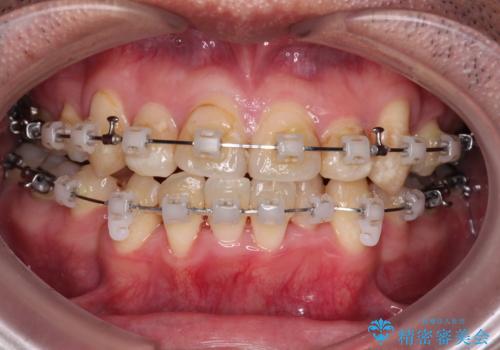

- 矯正装置

- クリアブラケット

上下ともに八重歯が顕著であったので、上下左右第一小臼歯4本を抜歯し、ワイヤー装置にて矯正治療を行うこととしました。